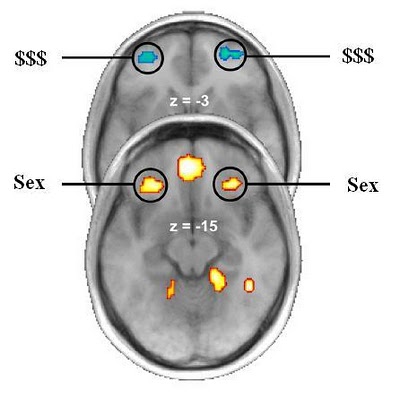

La cuestión es que, aún respondiendo a cualquier estÃmulo tipo recompensa, se sugiere que cuanto más primitiva es ésta, más probable es que se active la parte posterior del OFC, evolutivamente anterior. Los estÃmulos abstractos, como el dinero, en cambio, deberÃan activar las partes anteriores, más modernas evolutivamente.

La imagen que ilustra el resultado resulta clarificadora. La entenderás, seas aficionado a la neurociencia o no.

Se comprueba en efecto la relación entre los estÃmulos primitivos y la región posterior del OFC, asà como la existente entre los estÃmulos abstractos en la región anterior. Por supuesto, siempre que aceptemos que el dinero es en efecto algo más abstracto que el sexo.